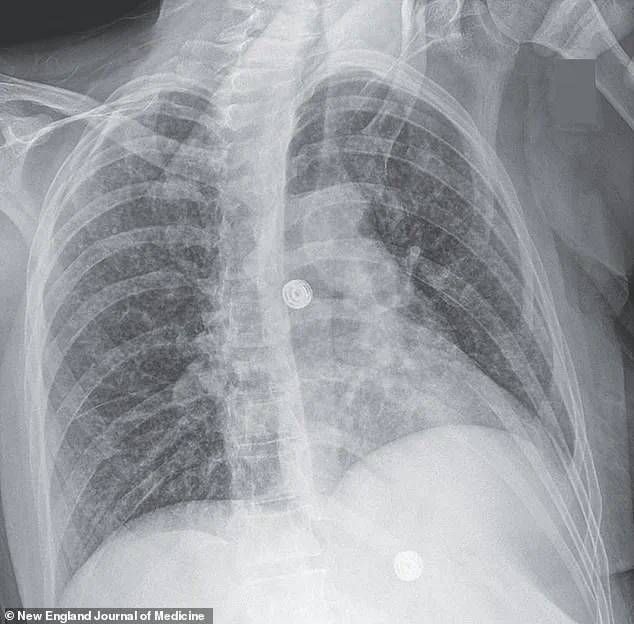

X-ray scans conducted during her stay uncovered small nodules in her lungs, a finding suggestive of bacterial infection.

Further imaging revealed lesions in multiple organs, including the liver, lymph nodes, pancreas, and brain—indications of a systemic infection.

In its early stages, the disease often presents with a persistent, unexplained cough, sometimes accompanied by coughing up blood or chest pain.

Patients may also experience unexplained weight loss, loss of appetite, fever, and night sweats.

If left untreated, the infection can progress to severe respiratory failure, extensive lung damage, and even the spread of bacteria to other organs, such as the brain, liver, and pancreas.